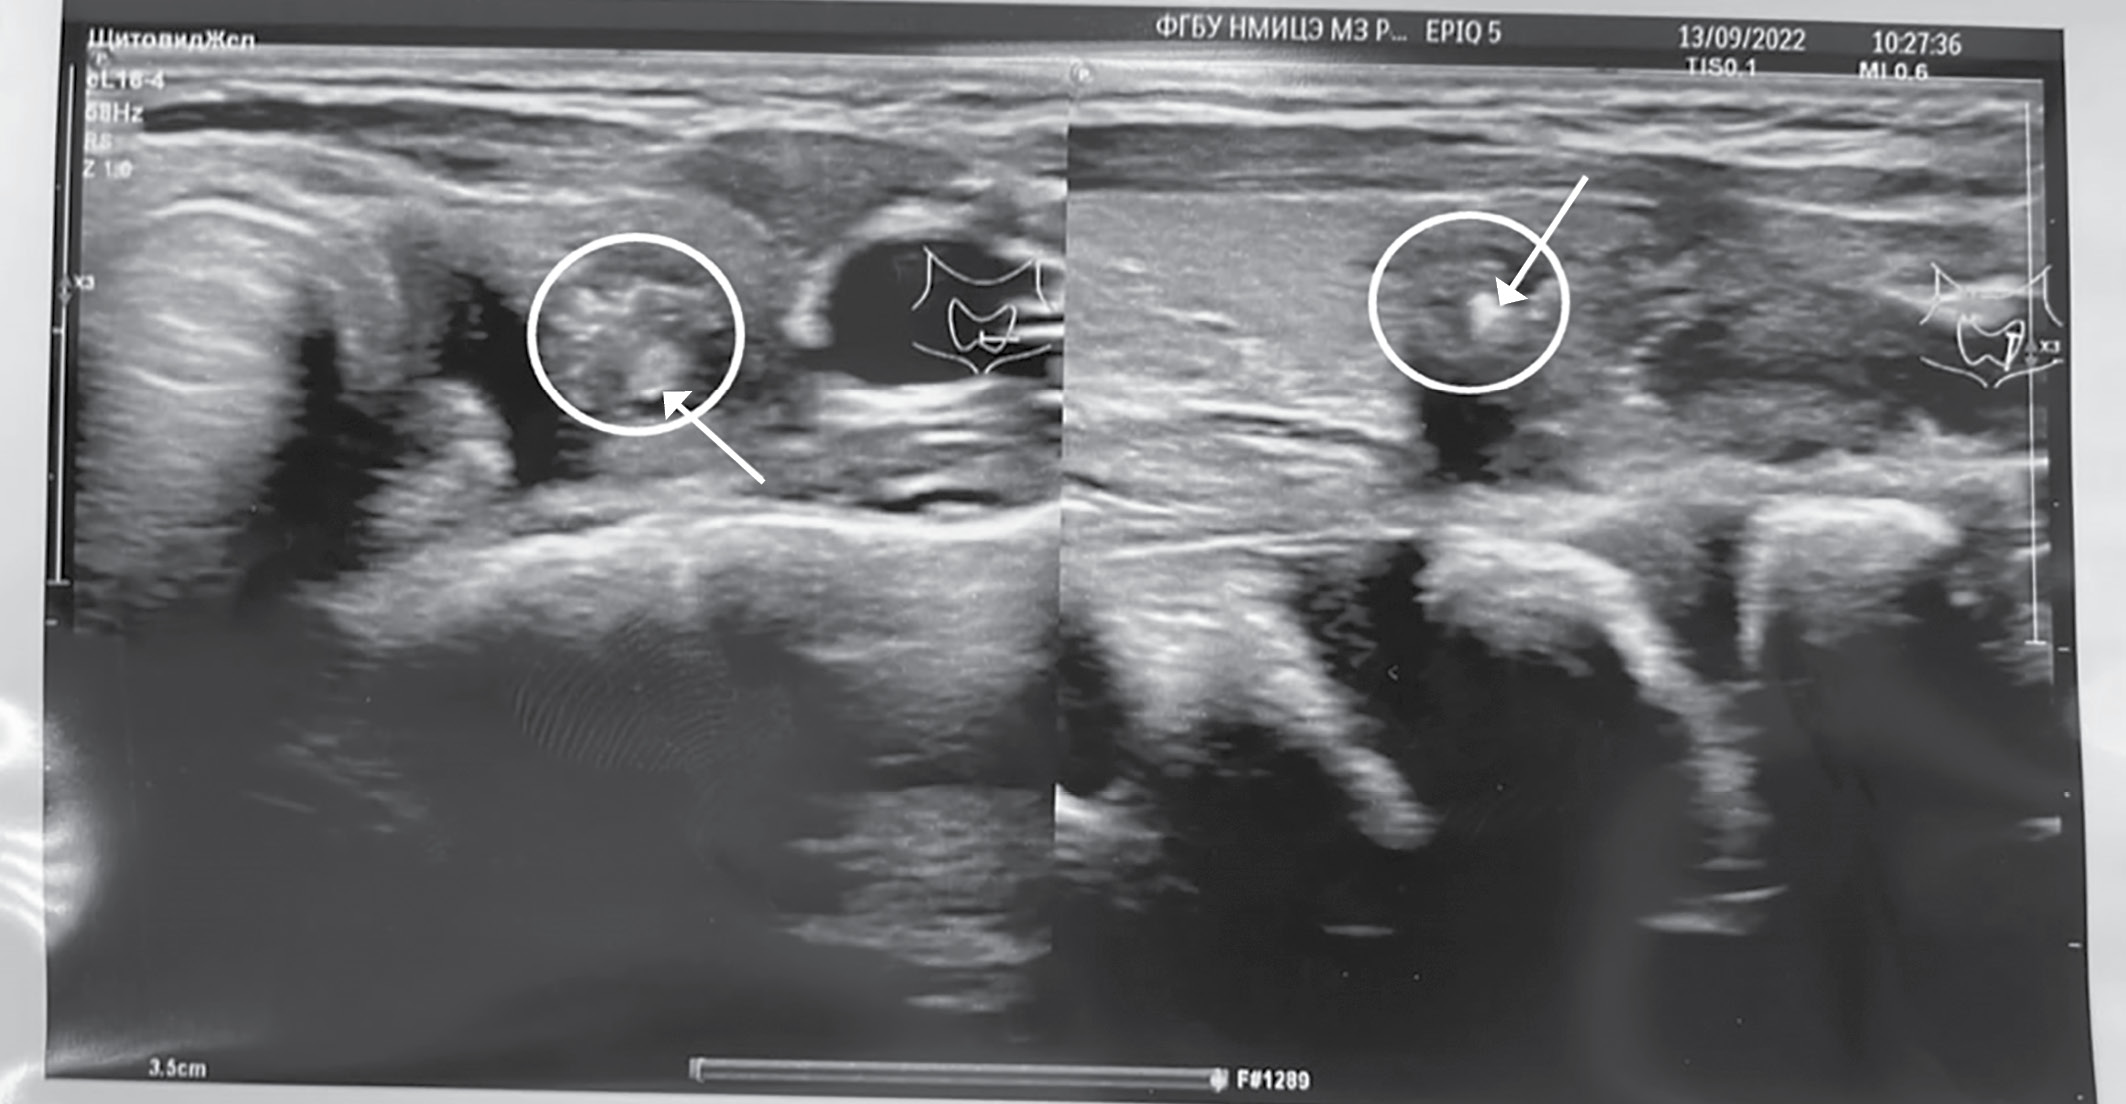

При морфологическом исследовании в левой доле щитовидной железы данных за опухолевый рост не получено, обнаружен обширный участок фиброза с наличием гранулематозного воспаления с гигантскими многоядерными клетками, лимфоцитами с примесью нейтрофилов, а также элементы участка протока с щелевидным просветом, выстланного многорядным эпителием среди лейкоцитарного инфильтрата (рис. 4).

Рисунок 4. Микроскопическое исследование

операционного материала левой доли щитовидной железы:

а — фиброзная ткань;

б — участок гранулематозного воспаления;

в — незаращенный щито-язычный проток;

г — инфильтрация гигантскими многоядерными клетками, лимфоцитами

с примесью нейтрофилов.

Окраска гематоксилином и эозином х50.

Figure 4. Microscopic examination

of the surgical material of the left lobe of the thyroid gland:

а — fibrous tissue;

б — area of granulomatous inflammation;

в — unfused thyroglossal duct;

г — infiltration of giant multinucleated cells, lymphocytes

with an admixture of neutrophils.

Staining with hematoxylin and eosin x50.